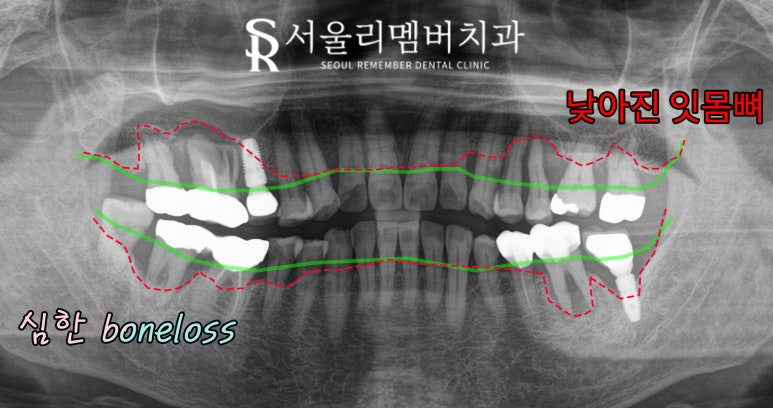

사당역 치과 에서 초록색 줄로 표시해둔 부분은

정상 치조골 높이인데,

이 케이스는 치주 질환으로 인하여

잇몸뼈가 퇴축되고 내려가면서

빨간색 줄로 표시해둔 부분까지

뼈가 녹아버렸습니다.

이럴 경우 치주 인대가 모두 사라지게 되면서

동요도가 커지게 되는데,

치근 끝까지 녹았을 경우

3도 이상의 심각한 흔들림이 발생되기에

이때는 발치를 해야 됩니다.